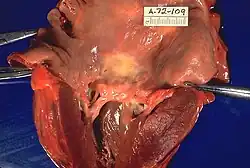

| Rheumatic heart disease at autopsy with characteristic findings (thickened mitral valve, thickened chordae tendineae, hypertrophied left ventricular myocardium) | |

Rheumatic heart disease

Chronic rheumatic heart disease (RHD) is characterized by repeated inflammation with fibrinous repair. The cardinal anatomic changes of the valve include leaflet thickening, commissural fusion, and shortening and thickening of the tendinous cords.[16] It is caused by an autoimmune reaction to Group A β-hemolytic streptococci (GAS) that results in valvular damage.[17] Fibrosis and scarring of valve leaflets, commissures and cusps leads to abnormalities that can result in valve stenosis or regurgitation.[18] The inflammation caused by rheumatic fever, usually during childhood, is referred to as rheumatic valvulitis. About half of patients with rheumatic fever develop inflammation involving valvular endothelium.[19] The majority of morbidity and mortality associated with rheumatic fever is caused by its destructive effects on cardiac valve tissue.[18] The complicated pathogenesis of RHD is not fully understood, though it has been observed to use molecular mimicry via group A streptococci carbohydrates and genetic predisposition involving HLA Class II genes that trigger autoimmune reactions.[20]